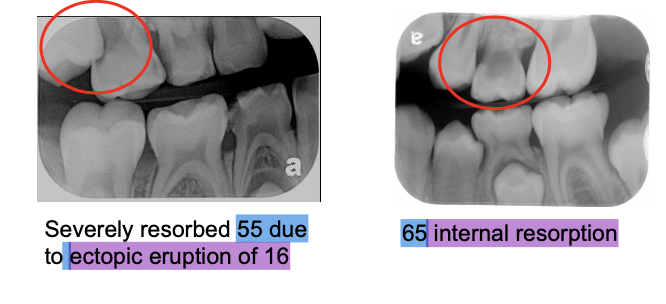

1. Indications and Rationale for Extraction of Deciduous Teeth (IRET)

IRET – Infections, Restore, Extraction, Trauma

Infections (odontogenic infections, irreversible pulpitis, pulpal necrosis)

Restore (hopeless prognosis, internal resorption, external resorption)

Extraction due to severe resorption (ectopic eruption, retained roots)

Trauma-related infection (alveolar abscess)

A